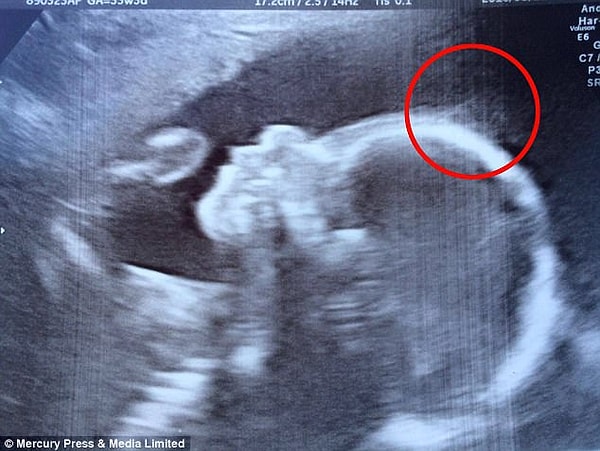

Эта малютка родилась с такими пышными волосами, что их было заметно даже на ультразвуке, когда она еще была в мамином животике! 28-летней Наташе Гент из английского города Кент врачи сказали, что 'ожидается много волос', когда увидели на экране УЗИ пучки на голове 20-недельного зародыша во время обследования.

4. Ранние признаки: врачи обнаружили волосы на голове Холли при 20-недельном сканировании